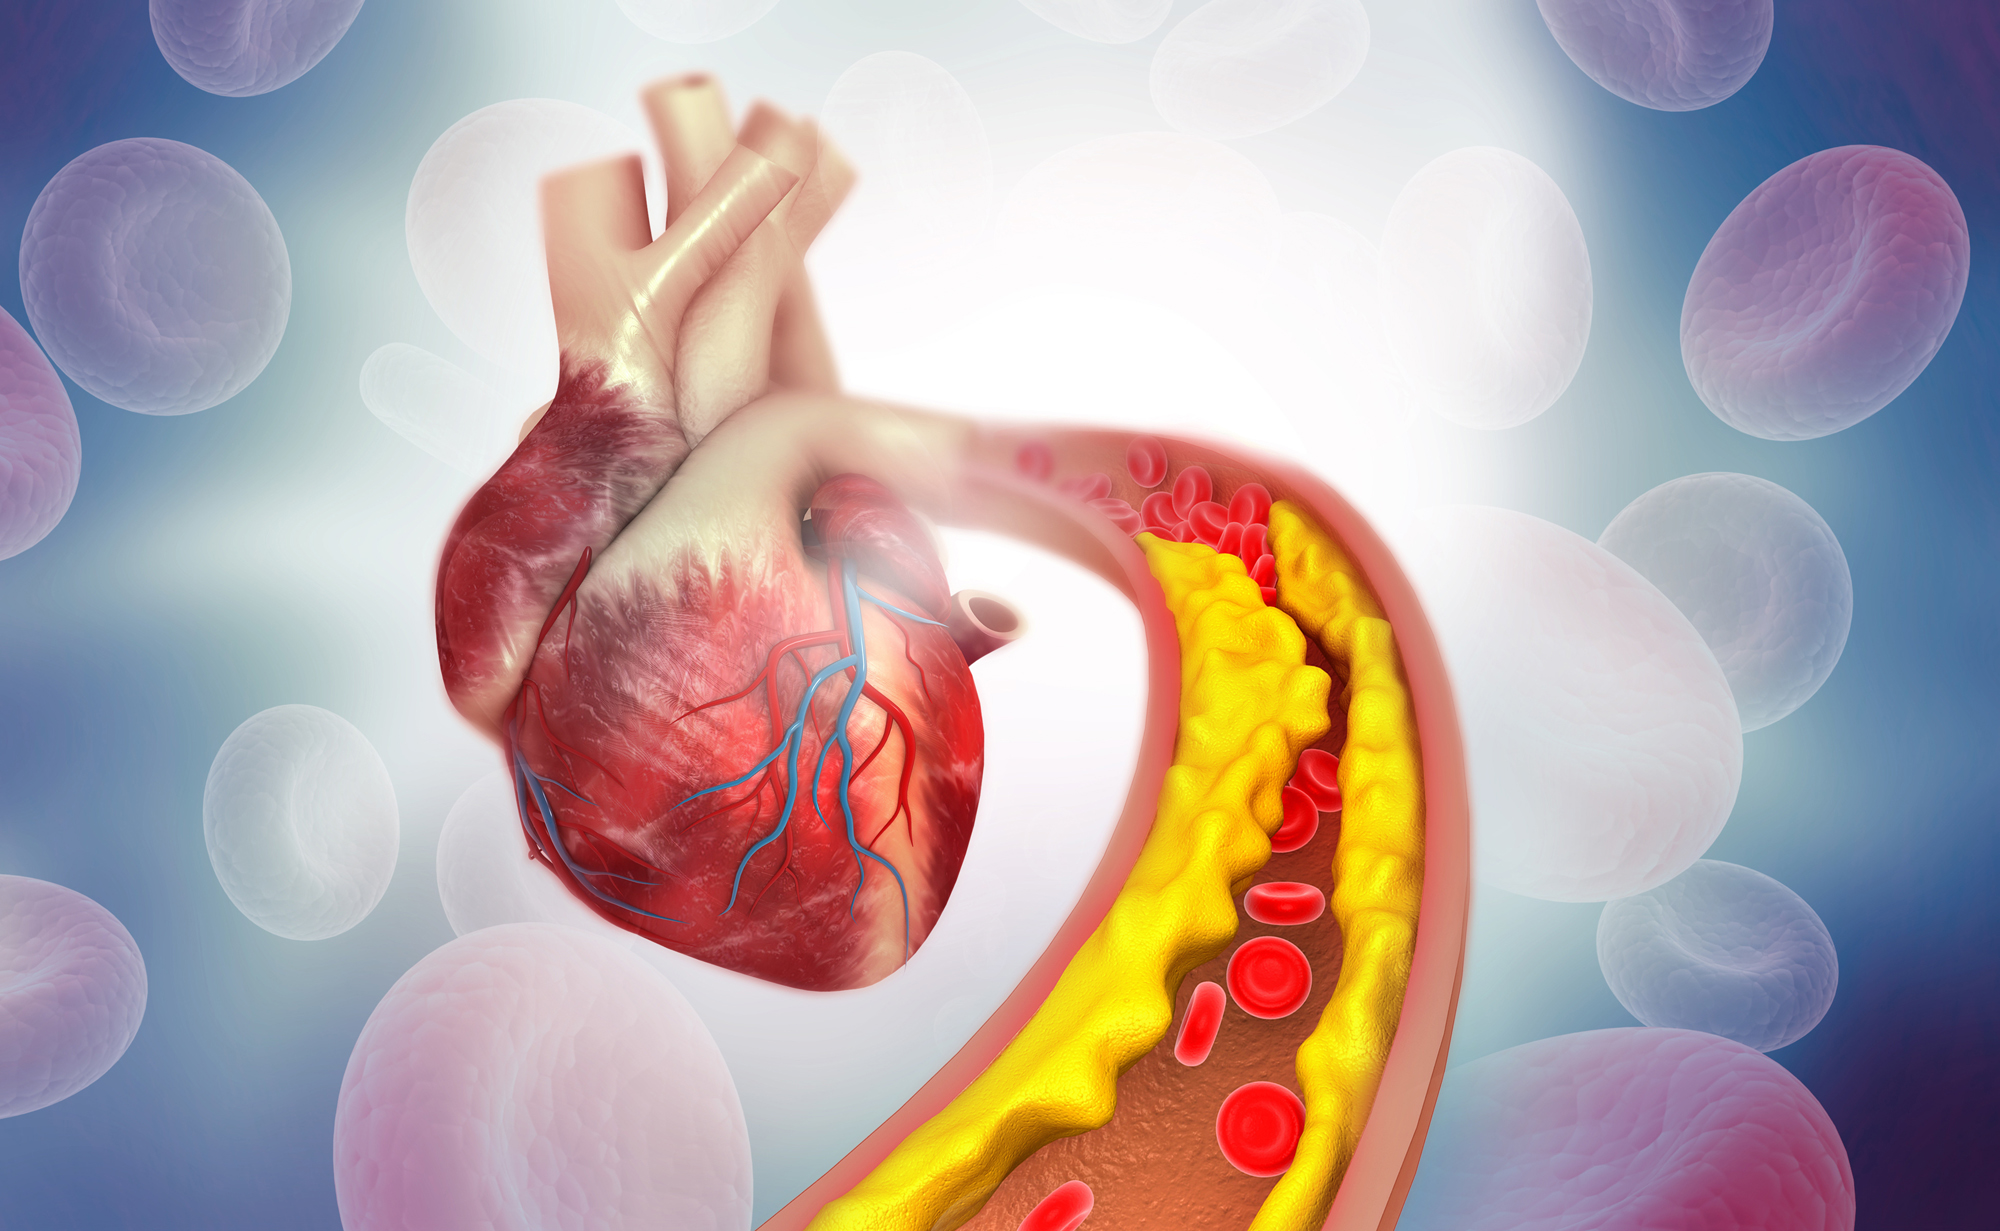

LDL-Cholesterin durch natürliche Mittel senken

Ein zu hoher Anteil von Blutfetten kann schwere Erkrankungen begünstigen. Gleichzeitig ist Cholesterin aber ein wichtiger Stoff für den menschlichen Körper. Es gilt, das „richtige“ Cholesterin zu fördern.